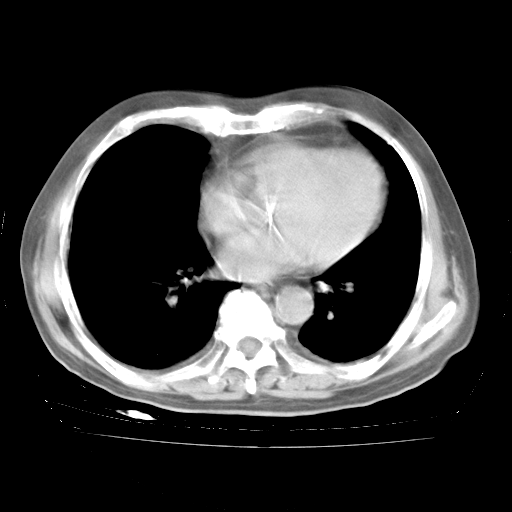

4月28日肺部CT——再次出现类似去年5月9日——透光度降低,“间质性”改变。

4月28日肺部CT——再次出现类似去年5月9日——磨玻璃样、间有“粟粒样”改变。

个人阅读4.14日肺部CT平扫:纵隔窗无异常,但肺窗示:双下肺内、后基底段有片絮状侵润影,部位以后基底段为著,以间质改变为主,呈急性肺泡炎征像,和首次住院影像学有相似之处。仅是个人读片,明日请相关专家再读片哈。其它建议同上。